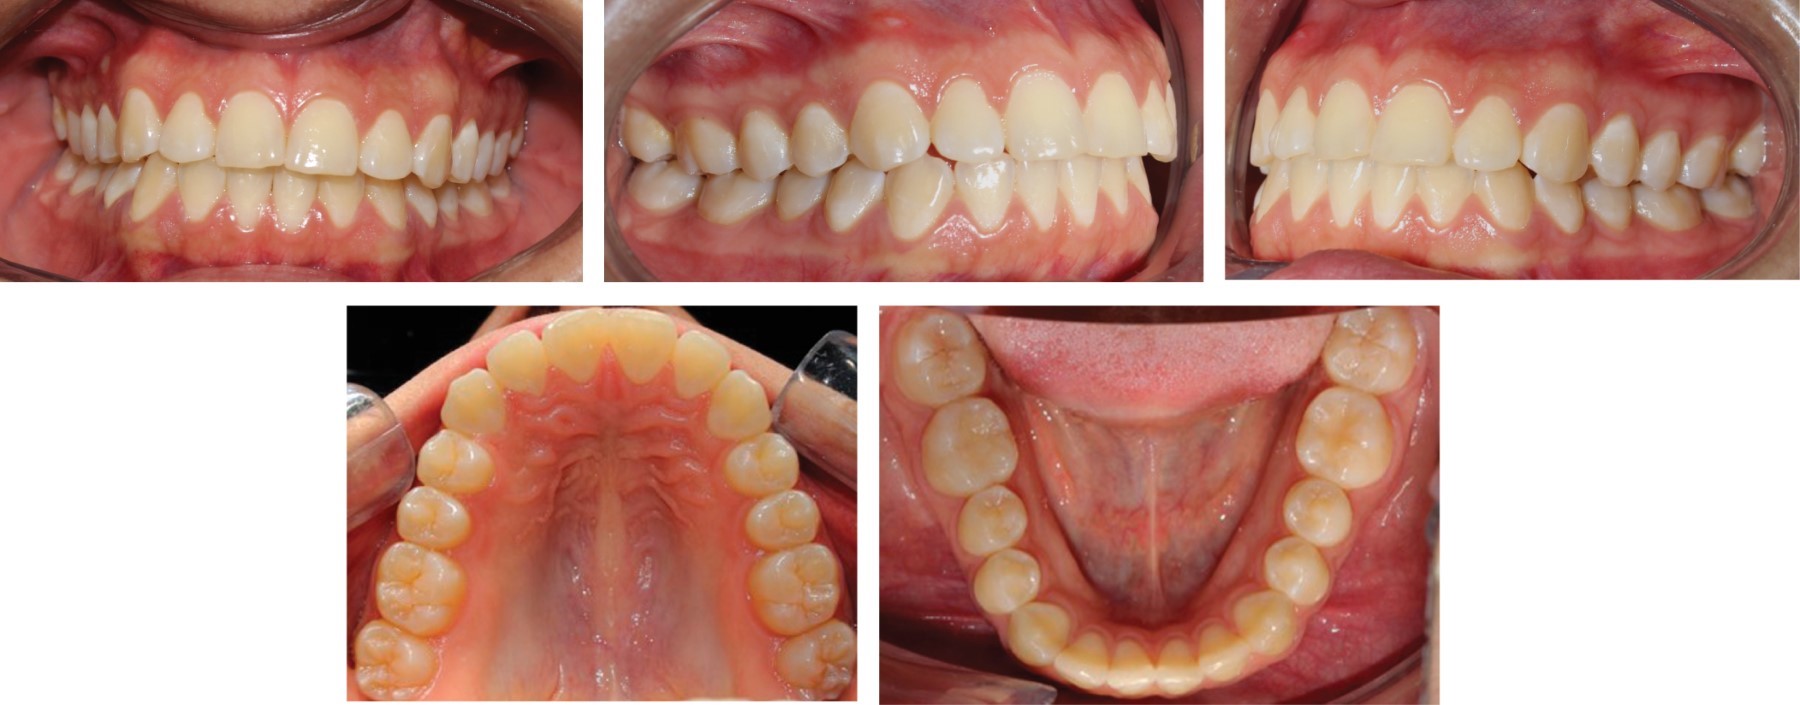

Paciente femenino de 24 años que acude a Clínica de Ortodoncia en la Escuela Nacional de Estudios Superiores Unidad León para corregir un canteamiento evidente. No presenta enfermedades crónicas ni datos patológicos que interfieran con el tratamiento. Diagnóstico: clase I esquelético biprotrusiva con crecimiento neutro, facialmente es una paciente braquifacial con perfil recto y retroquelia, se observó asimetría facial en la comparación del lado izquierdo y derecho. Incisivos superiores proinclinados, giroversiones, clase molar III derecha e izquierda, clase I canina bilateral, línea media desviada y plano maxilar canteado donde se observa que se necesita una intrusión de 5 mm para corregirlo (Figuras 1, 2 y 3).

Fase 3: mecánica principal, arco 0.019" × 0.025" SS superior y 0.016" × 0.025" SS inferior (Figura 4).

Los resultados a los tres meses de revisión fueron satisfactorios, se observa una intrusión evidente, resultados de la biomecánica tal como la mordida abierta posterior, que se fue solucionando con diferentes métodos y teniendo control de torque en todo momento (Figuras 5, 6, 7 y 8).

Figura 3

Figura 4

Figura 5